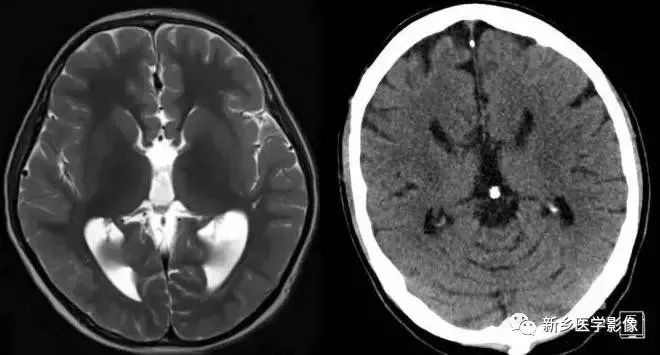

❶ 导水管狭窄

中脑导水管是脑室系统最狭窄的通道,也是脑脊液循环受阻最常见的部位。

导水管粘连主要见一于颅内感染和出血后,可于胚胎期发生,也可见于出生后任何年龄。导水管粘连所致狭窄多位于导水管远端。狭窄段长度通常为2一5mm,狭窄近端异水管可呈喇叭口样扩张。

导水管狭窄时,三脑室扩大常很显著,三脑室前部视隐窝和漏斗隐窝扩张或消失,三脑室后部松果体隐窝和松果体上隐窝明显后突,向小脑上池疝入。严重者可压迫小脑。